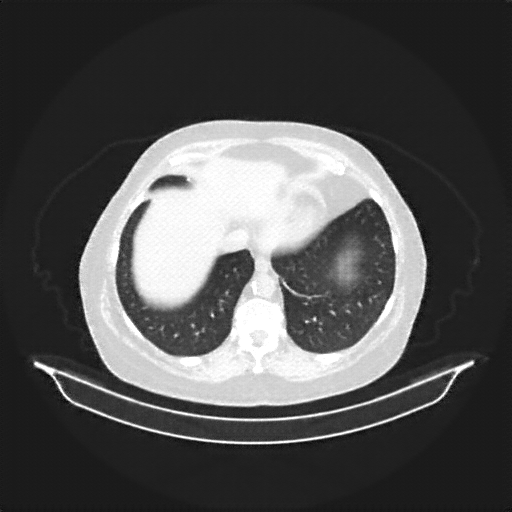

Image Grid

4Γ—3 grid: Rows show different image types (Original NATIVE, Reconstructed NATIVE, Original VENOUS, Generated VENOUS), Columns show windowing techniques (No Window, Lung Window, Mediastinum Window)

Original NATIVE CT scan (input)

Full window (WL 1023.5, WW 4095 β†’ Low βˆ’1024, High +3071)

Actual HU range: [-1024.0, 1049.0]

Lung window (WL -600, WW 1500 β†’ Low βˆ’1350, High +150)

Actual HU range: [-1024.0, 150.0]

Mediastinum window (WL 40, WW 400 β†’ Low βˆ’160, High +240)

Actual HU range: [-160.0, 240.0]